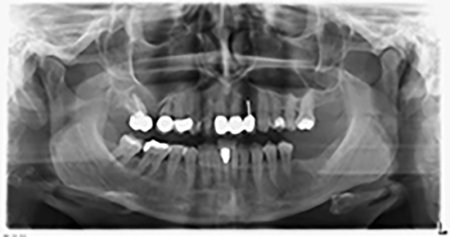

About six months after teeth 16 and 14 were extracted, a digital volume tomography (DVT, Planmeca) examination was performed for planning and risk minimization purposes. It clearly showed that the bone had not regenerated to the desired volume (Fig. 2 to 7).

Image 2 to 7: DVT with greatly reduced horizontal bone volume.

A sinus floor elevation is required in both region 16 and region 14 to guarantee a fixed restoration based on at least two implants. Relatively large-scale bone augmentation is required due to the residual bone volume being extremely low in this case. Major bone augmentation procedures are invasive and linked to higher patient morbidity, as well as being time-consuming and expensive. It is more difficult to predict the results of the treatment and the risk of failure is increased. The patient was informed of the increased risk and was offered a removable solution, which she consistently rejected.

To restrict the augmentation to region 14, and in consultation with the patient, it was planned that implant 16 would be placed, inclined, in the dorso-cranial direction (Fig. 8).